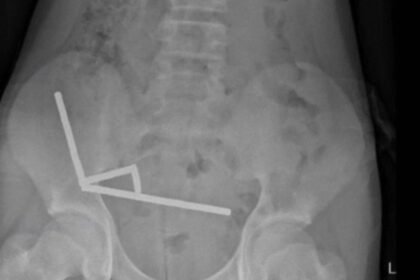

Tauranga Hastanesi’nde karın ağrısı şikayetiyle tedaviye alınan çocuk, yaklaşık bir hafta önce 100 kadar neodim mıknatıs yuttuğunu söyledi. Ancak yapılan ameliyatta midesinden çıkarılan mıknatıs...